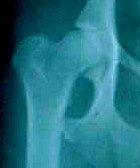

Figure 2  A normal canine hip with the desired 130-degree angle.

Here are a few examples of hip evaluation IN BEAGLES from OFA.

As you look at these pictures, try to imagine the angle, the smoothness and length of femur neck and the roundness of the femoral head.  Draw two imaginary lines, one from the top rim of the acetabulaum to the outer edge and another line depicting the angle.

OFA EXCELLENT

OFA GOOD

OFA FAIR